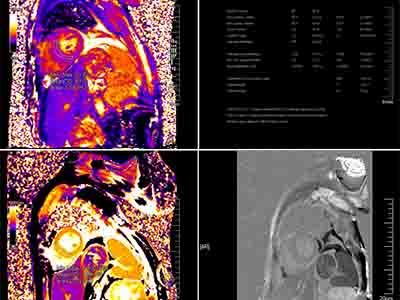

医学影像中心三院区总占地面积约2300多平方米,配备了先进的医学影像设备,3.0T核磁2台、64排及以上CT4台、胃肠X光机1台、DR1台、口腔全景1台、口腔CT1台及移动DR2台,包括西门子Lumina 、双源Force CT、联影高端uCT960+等;另配备国内高端PACS网、报告书写可调节桌椅等软硬件设施。现有职工20人,硕士研究生学历10人,本科10人。其中诊断医师12名,其中副主任医师3名,主治医师7名,初级医师2名。技师7名,其中副主任技师1名,主管技师2名,初级技师4名。主管护士1名。团队具备丰富的临床经验及学术造诣,能够为患者提供精准的医学影像诊断与咨询服务。与临床科室紧密合作,能够针对血液病患者提供个性化的影像检查和诊断服务,开展了许多新技术、新方法,如心脏淀粉样变性、心脏铁沉积、肝脏铁沉积、全身低剂量CT、全身MRI检查、经皮穿刺活检操作等,以满足患者多元化需求。

核磁共振铁过载测量

通过核磁共振成像技术,对心脏,肝脏,肾脏等铁过载的程度及定量评估

全身磁共振成像技术

全身磁共振的形态学与功能成像技术